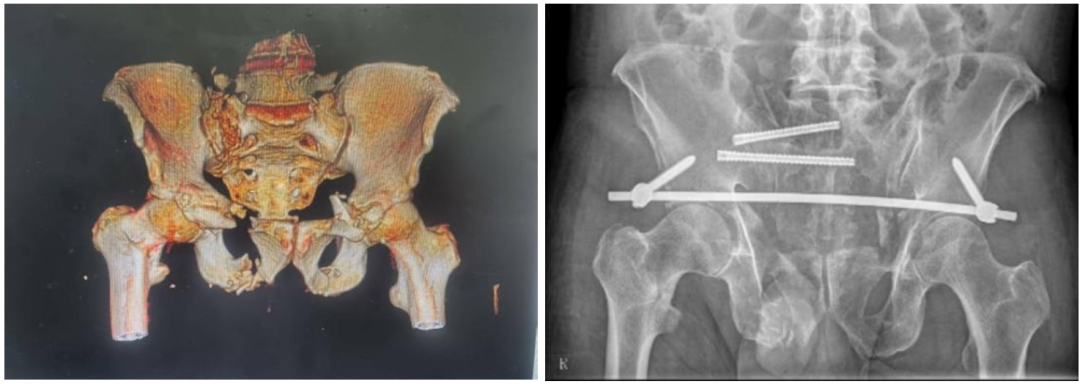

术前CT检查及术后X线检查。(翻拍图片)

术中在机器人的导航下顺利植入骶髂螺钉。

李宏彦、曲高伟两位副主任医师共同为患者施行手术。整台手术的出血量仅30毫升,术后患者很快苏醒,双下肢感觉与活动均无异常。